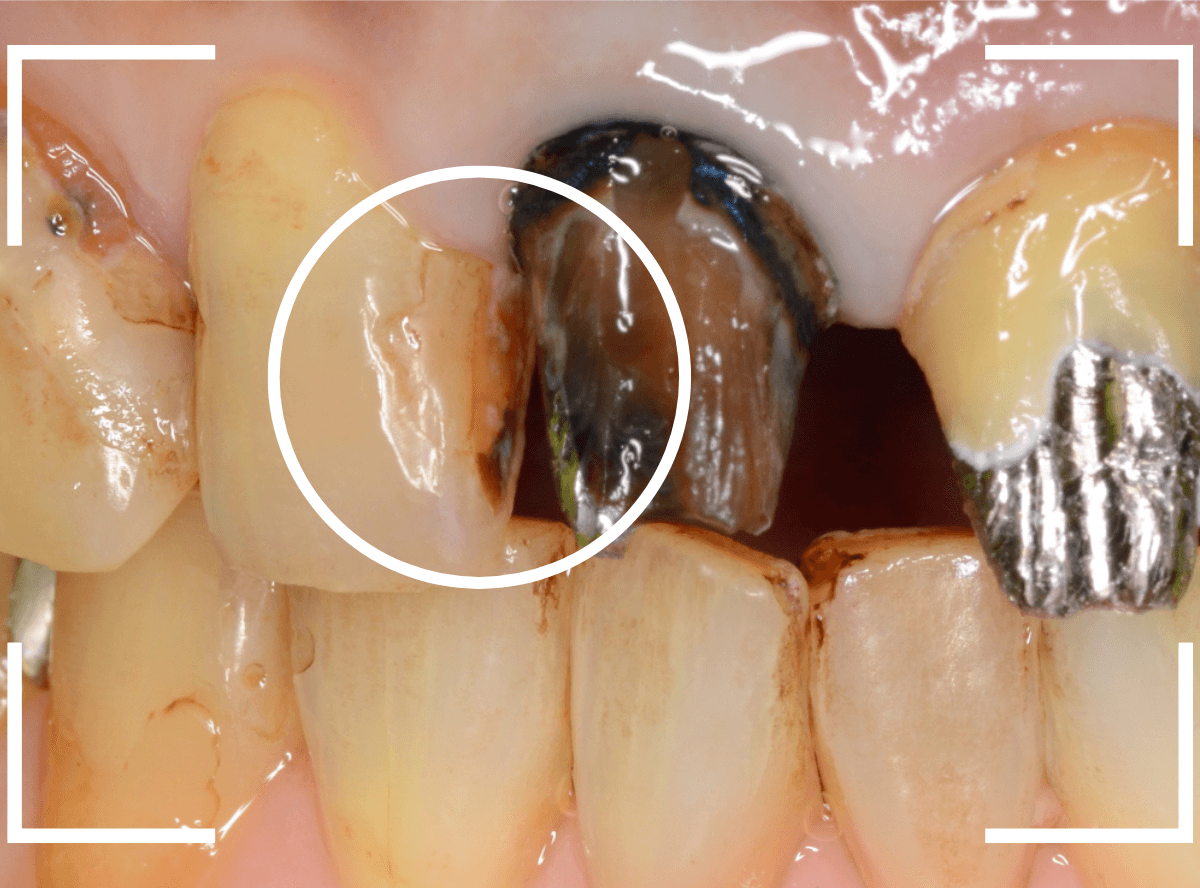

今回は、上の奥歯の銀歯(メタル・クラウン)の中で虫歯になってしまった方です。

通常は、さし歯の中が虫歯になってしまうと、レントゲンにも写らず見つけづらいのですが・・・。

歯を裏側から見たところです。

幸い、見える部分に虫歯が

さし歯と歯肉の間に虫歯ができているのがわかります。

歯の奥まで虫歯が進んでいるのか、浅い虫歯ですんでいるのかは治療をしながら調べていく必要があります。

さし歯を外すと、金属の土台(メタル・コア)が出てきました。

慎重に土台を外して、中を調べます。